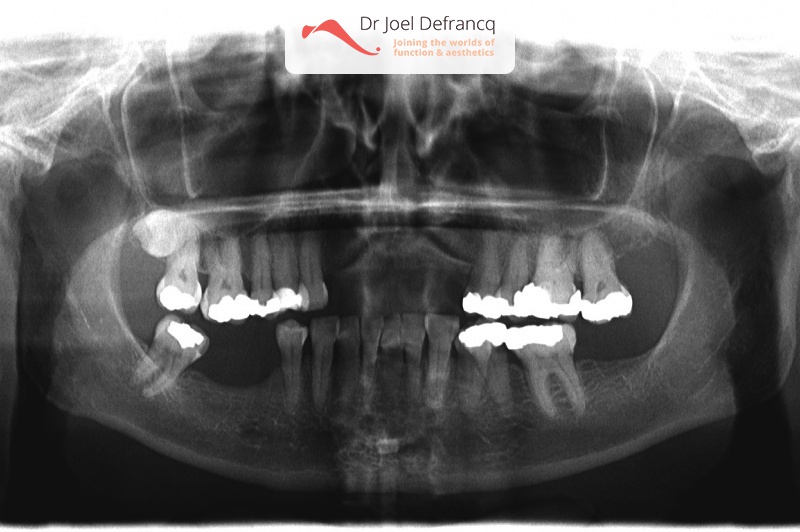

Axelle: new teeth in a week - implants.

Behandeling tandheelkundige implantaten

- Vaste tanden op implantaten (bovenkaak)